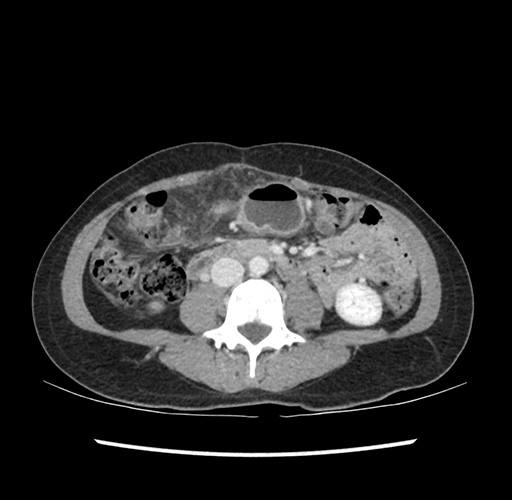

Imaging Analysis

Look through the patient's CT scan to identify any areas of concern for the necessary procedure.

Based on your CT findings, which issue(s) would give reason for "planned slowing down moment(s)" in this case?

Considering a standard left lateral sectionectomy procedure, what step(s) of the operation would you do differently in this case ?